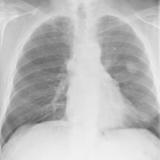

Case 8a Thymoma PA

Date: 03/27/2009

Views: 9449